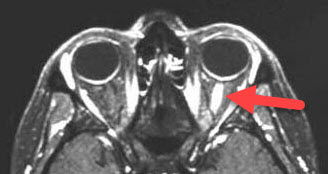

Inflammed Optic Nerve on an MRI Scan

A comprehensive dilated eye exam is performed looking for optic nerve swelling, although this is usually absent or mild. Often the nerve inflammation can occur behind the eye, making it difficult to find during your eye exam. Color vision and visual field testing are often abnormal. An MRI scan of the optic nerves and the brain is usually diagnostic. The MRI is also useful in ruling out many other problems that can cause optic nerve swelling such as pseudotumor cerebri (idiopathic intracranial hypertension), tumors, and infections.